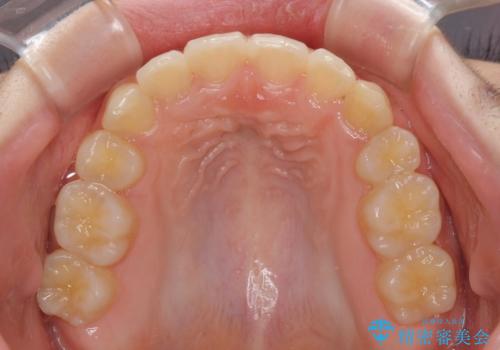

下顎の乳歯は永久歯と比べて幅が大きいため、抜歯した場合のスペースが大きく、治療には長期間を要することが一般的です。

今回の患者様は中学生ということもあり、成人の患者様と比べ動きが速く、2年間で治療を終えることができました。